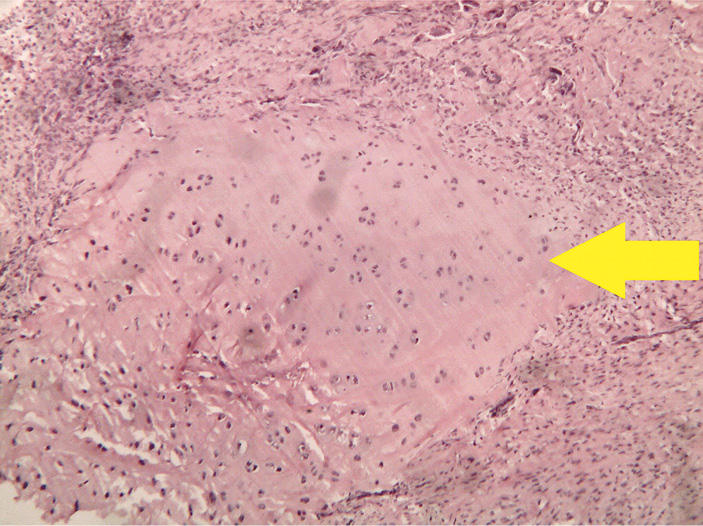

- Группа с губчатым материалом на основе хитозана и гидроксиапатита (рис. 5).

Рис. 5. Группа с протезом из хитозана с гидроксиапатитом: хрящевые островки среди грубоволокнистой ткани в зоне костного дефекта. Окраска гематоксилином и эозином, увеличение ×40

На 28-е сутки в зоне дефекта наблюдается участок, заполненный грубоволокнистой соединительной тканью с многочисленными гигантскими клетками инородных тел, сформированными вокруг небольших очагов из остатков исследуемого образца. К грубоволокнистой соединительной ткани прилежит костная мозоль с небольшими и немногочисленными более крупными хрящевыми «островками».